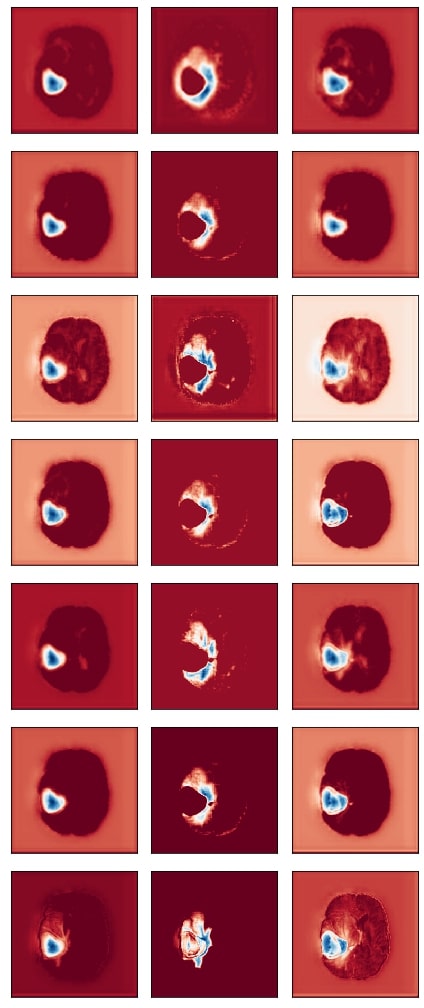

Refer to caption

Figure 5: This figure depicts the gradient based class activation maps obtained at selected intermediate layers of all the three networks in ascending order. (L:Layer, E:Encoding, B:Block, D:Decoding)

We posit that model complexity and residual connections might have an impact on how early a model can localize the tumor region. For example, the DenseUnet and ResUnet localize the tumor region in the first few layers, while the SimUnet, which has no skip or residual connections, localizes the tumor region only in the final few layers (Figure 5). This indicates that skip and residual connections help learn and propagate spatial information to the initial layers for faster localization. While previous literature indicates that skip connections allow upsampling layers to retain fine-grained information from downsampling layers (Jégou et al., 2017), (Drozdzal et al., 2016), our results indicate that information might also be flowing in the other direction i.e. skip and residual connections help layers in the downsampling path to learn spatial information earlier.

Drozdzal et al. (2016) also discuss that layers closer to the center of the model might be more difficult to train due to the vanishing gradient problem and that short skip or residual connections might alleviate this problem. Our results support this as well - middle layers of the SimUnet, which does not have residual or skip connections, seem to learn almost no spatial information compared to the other two networks (Figure 5a).

Our results in Figure 5 also show that models take a largely top-down approach to localizing tumors - they first pay attention to the entire brain, then the general tumor region, and finally converge on the actual finer segmentation. For example, attention in all three models is initially in the background region. In the DenseUnet and ResUnet, attention quickly moves to the brain and whole tumor within the first few layers. Finer segmentations are done in the final few layers. The necrotic tumor and enhancing tumor are often separated only in the last few layers for all models, indicating that segregating these two regions might require a lesser number of parameters.

This top-down nature is consistent with theories on visual perception in humans - the global-to-local nature of visual perception has been documented. (Navon, 1977) showed through experiments that larger features take precedence over smaller features, called the Global Precedence Effect. While this effect has its caveats (Beaucousin et al., 2013), it is generally robust (Kimchi, 2015). Brain tumor segmentation models seem to take a similar top-down approach, and we see in our experiments that such behavior becomes more explicit as model performance improves.